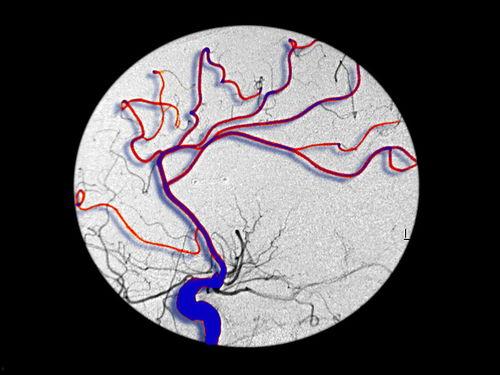

首先,我们来聊聊什么是脑出血。脑出血,顾名思义,就是大脑内部血管破裂,血液流入脑组织或脑室。这种疾病发病急骤,病情严重,甚至可能危及生命。那么,脑出血患者能不能吃瓜呢?